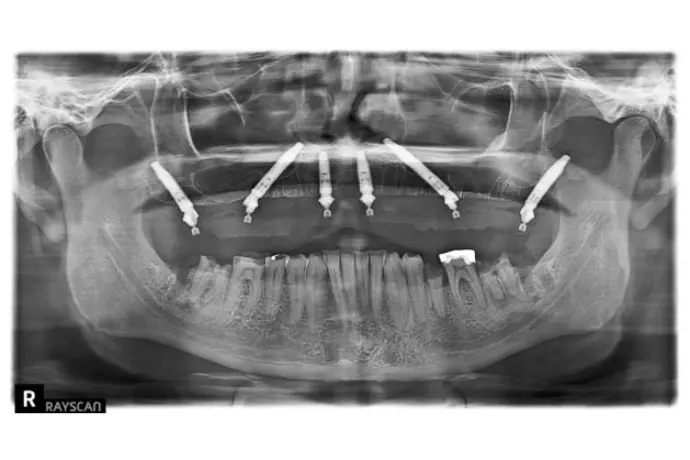

Référentiel Full Arch Club : All-on-4, All-on-X, palatal approach, trans-sinus, pterygoïdes, subpériostés personnalisés. Moins invasif, plus sûr.

• Chirurgie et mise en charge immédiate avec une approche sans greffes osseuse  et prédictible.

Opération chirurgicale en direct réalisée par le Dr Bernardo Nunes de Sousa